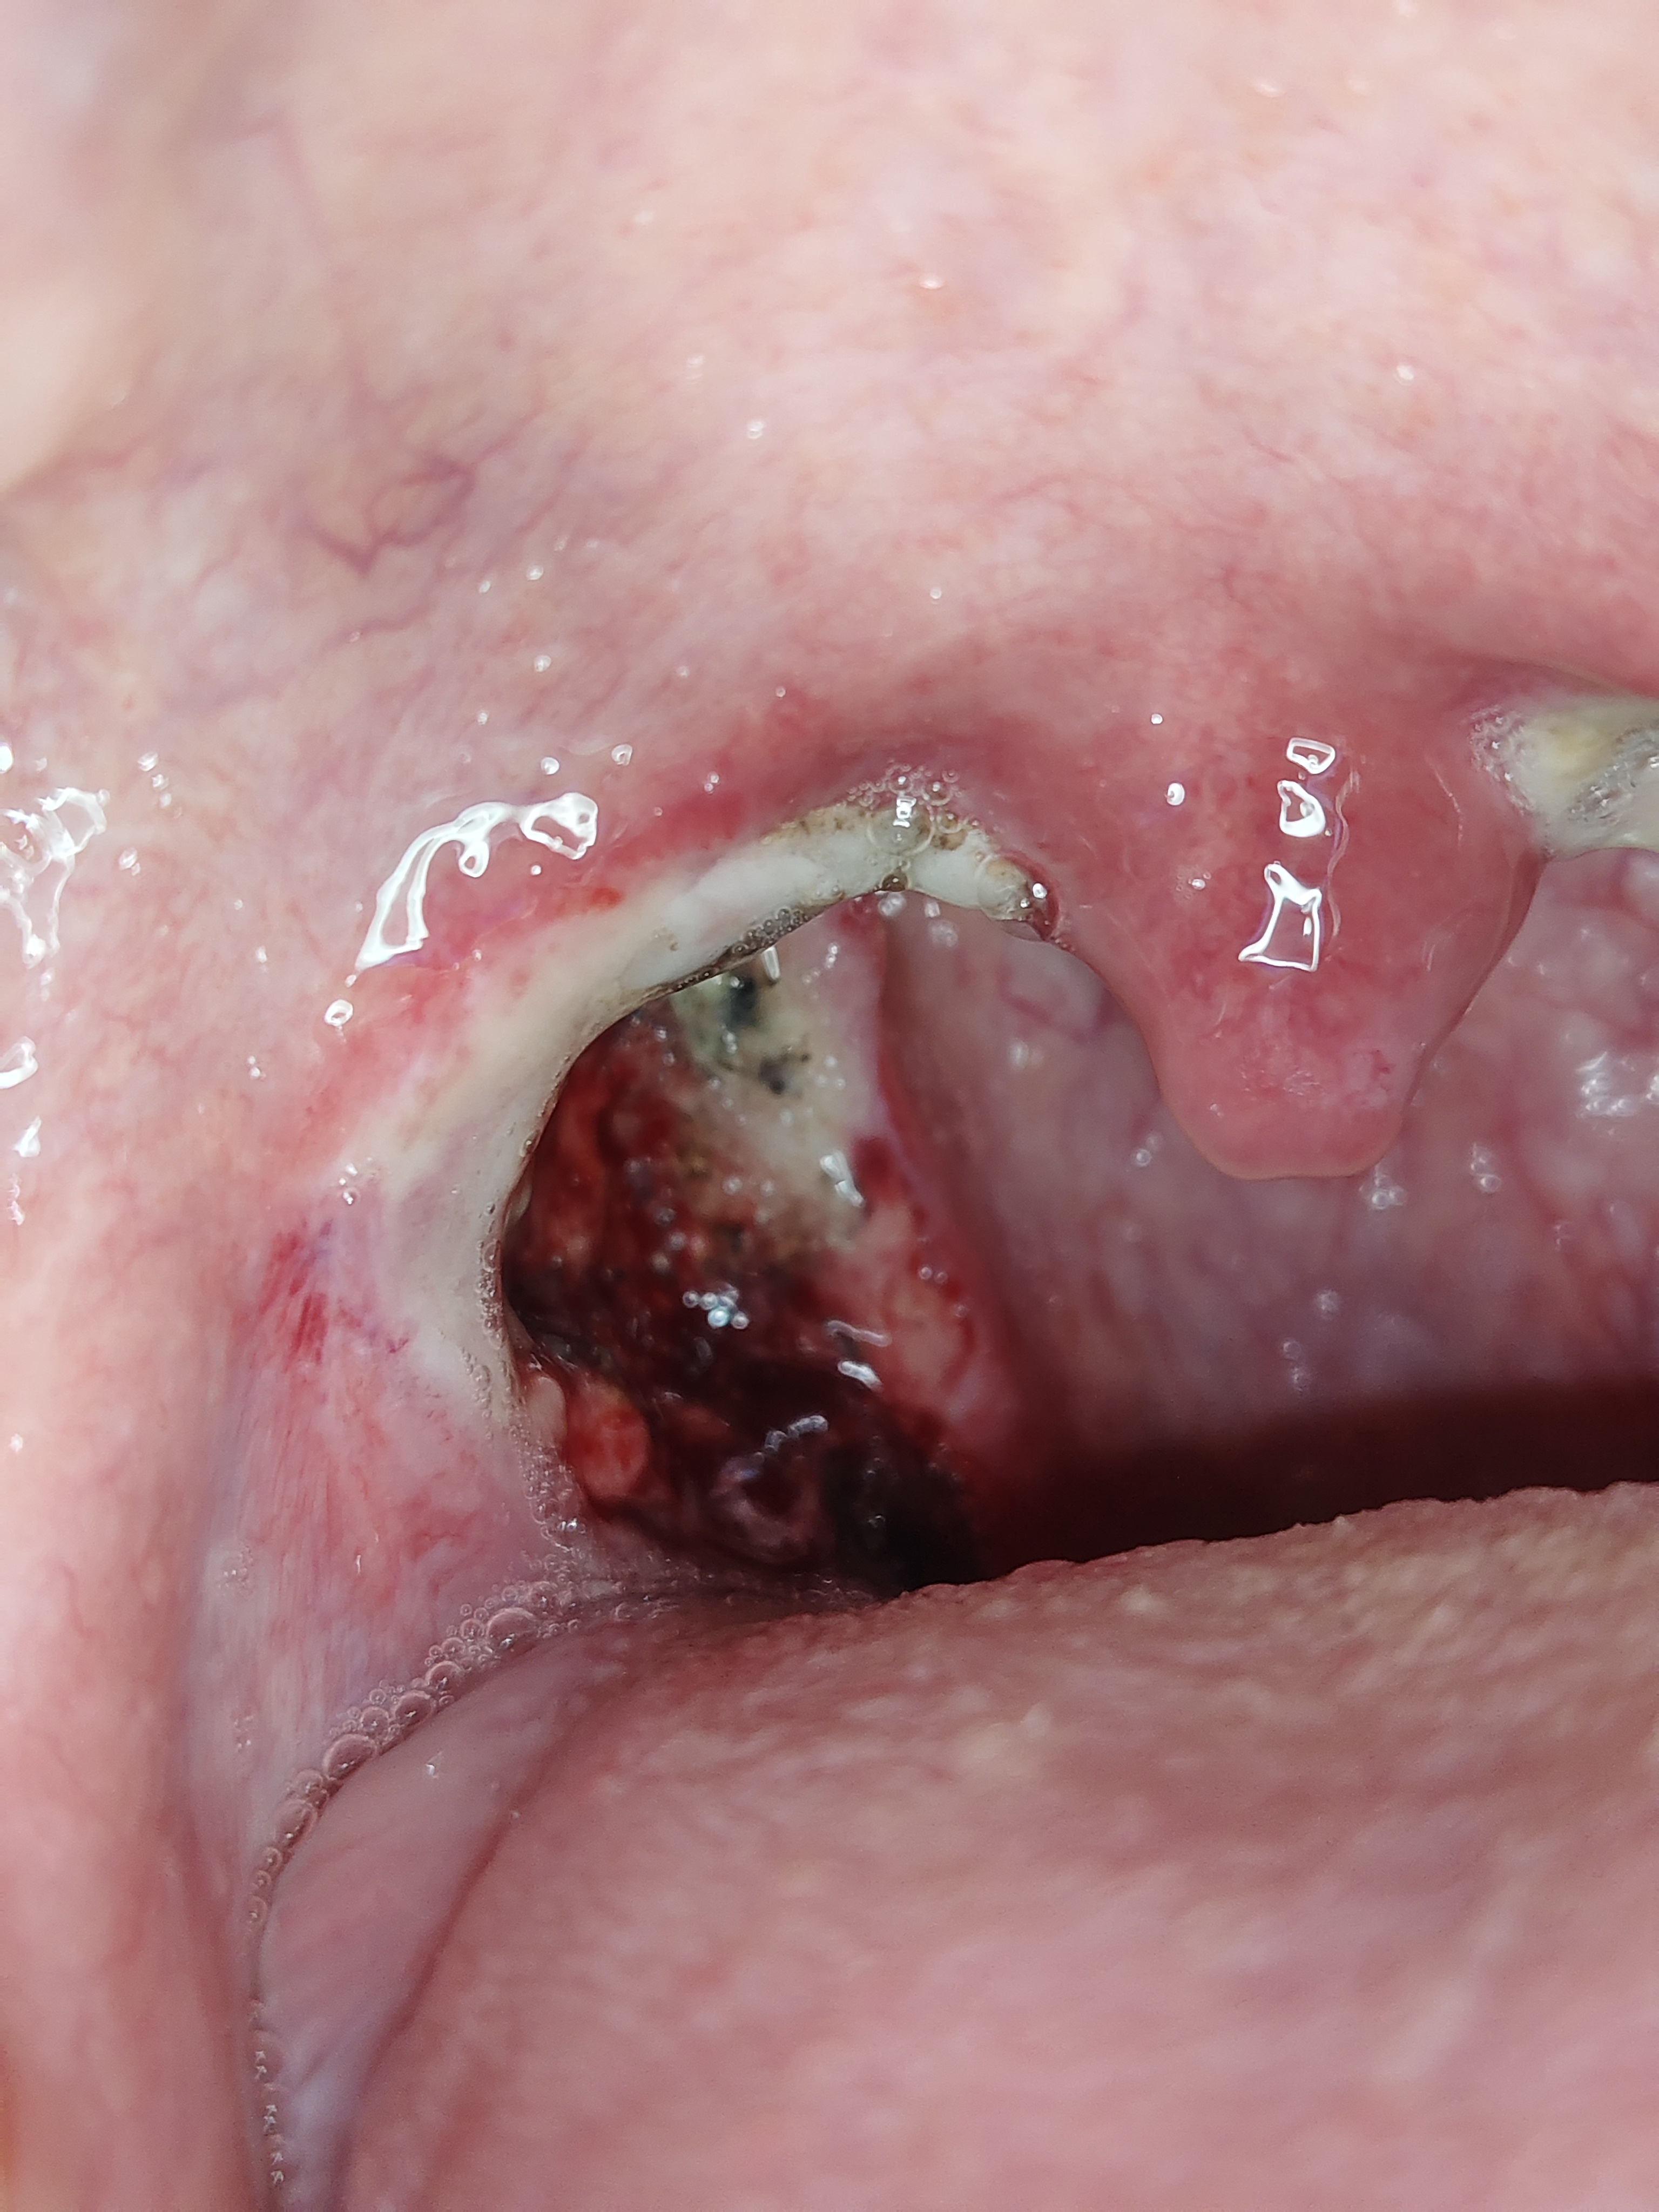

ผ่าตัดต่อมทอนซิลมาได้ 8 วัน วันนี้กินไอติมเข้าไปแล้วอาเจียนออก อยู่ๆ ก็เป็นแบบนี้ปกติไหม

อายุ: 27 ปี เพศ: F น้ำหนัก: 57 กก. ส่วนสูง: 155ซม. ดัชนีมวลกาย : 23.73 (ค่ามาตรฐานคนเอเชีย=18.5-22.9)

สะเก็ดแผลในปากจะเป็นสีขาวไม่เหมือนที่ผิวหนังจะเป็นสีดำ หลังจากผ่า 7 วัน สะเก็ดจะเริ่มลอก อาจมีเลือดออกได้ ห้ามกลืนเลือดลงท้องมันจะออกซึมๆไปเรื่อยๆ จนเสียเลือดมากได้ครับ ถ้าเลือดไม่หยุดต้องกลับไปพบแพทย์ครับ